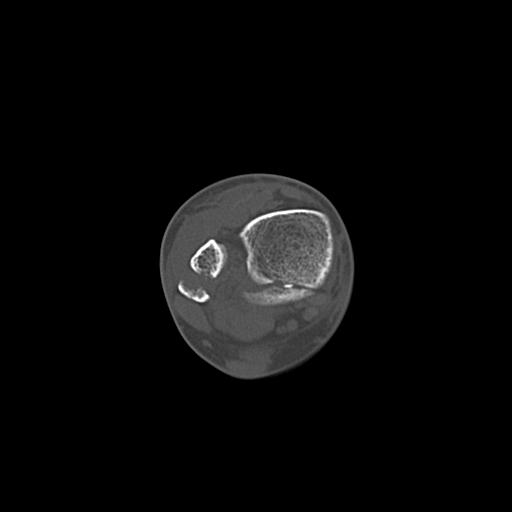

49554 3/13 膝 4R 3/16 4R 1/18 2R 78歳男性 膝蓋骨骨折